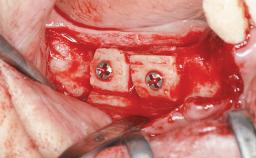

Ridge Preservation and Implant Placement for a Fixed Dental Prosthesis After a Car Accident

Mario Roccuzzo

It is well known to clinicians that any removal of teeth will, over time, cause the dimensions of the alveolar ridge to be reduced by resorption of the bundle bone and by changes related to external modeling. This development is particularly evident in the crestal region with its thin buccal bone that consists of bundle bone almost entirely. The facial bone will rapidly resorb as blood supply from the periodontal ligament gets disrupted (Araújo and Lindhe 2005). There is no reason why traumatic tooth loss should not have the same consequences. It takes more than achieving implant osseointegration for a treatment outcome to be considered successful. No deficiency of bone or soft tissue is acceptable when an ideal esthetic outcome is the goal. Several articles (Sanz and coworkers 2011; Vignoletti and coworkers 2011) have reported on techniques of improving the alveolar ridge for implant treatment, notably focusing on protecting tissues from resorption.